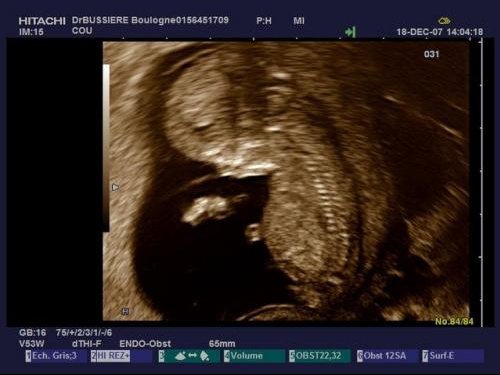

Battement coeur bebe fille garcon. Fille ou garçon. Mais je me surprends à chercher des indices là où il n y en a. Coucou j ai un petite question j ai entendu parler qu on pouvait savoir le sexe de bebe par rapport au battement de cœur par minute et qu ils faisaient comme ça dans le temps. Dans les temps anciens cette hypothèse avait une certaine part de probabilité car les gens remarquaient que dans le ventre de la mère le cœur des filles battait différemment du cœur des garçons.

Bonjour bb1 pour moi j ai eu une eco de datation avec 170 de battement de cœur par minute. Peut on vraiment savoir le sexe de bébé. Je ne sais pas si ca fonctionne réellement. Bien qu il n existe pas de test et de méthodes infaillibles certains signes pourraient vous mettre la puce à l oreille au fil des mois.

Battements du coeur. Selon vous filles ou garcon. Alors moi a 6 sa 3 son cœur battait a 127 bpm et a 8 sa 3 entre 160 et 180 bpm. Battement du cœur fille ou garcon.

Battement coeur foetus fille ou garcon. Deviner le sexe grâce au battement de cœur de bebe.